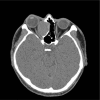

Patient concerns: We report a case of a 37-year-old man who presented with painless proptosis of the right eye and diplopia.

Diagnoses: The preoperative finding was mucocele of the ethmoid sinus.

Interventions: We performed endoscopic sinus surgery, which included uncapping of the anterior and superior wall of the mucocele.

Outcomes: The mucocele was treated safely and effectively without touching the medial orbital wall.